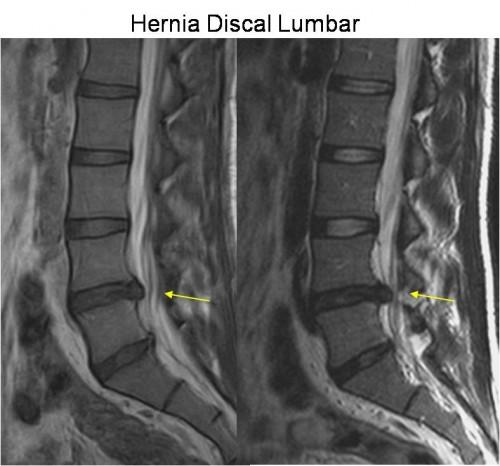

También es posible que el médico especialista recomiende un procedimiento de este tipo si la persona experimenta dolor de espalda o fiebre, lesiones o traumas en la columna lumbar, defectos congénitos de la columna lumbar, así como esclerosis múltiple, problemas para controlar o vaciar la vejiga o un problema con una hernia de disco.